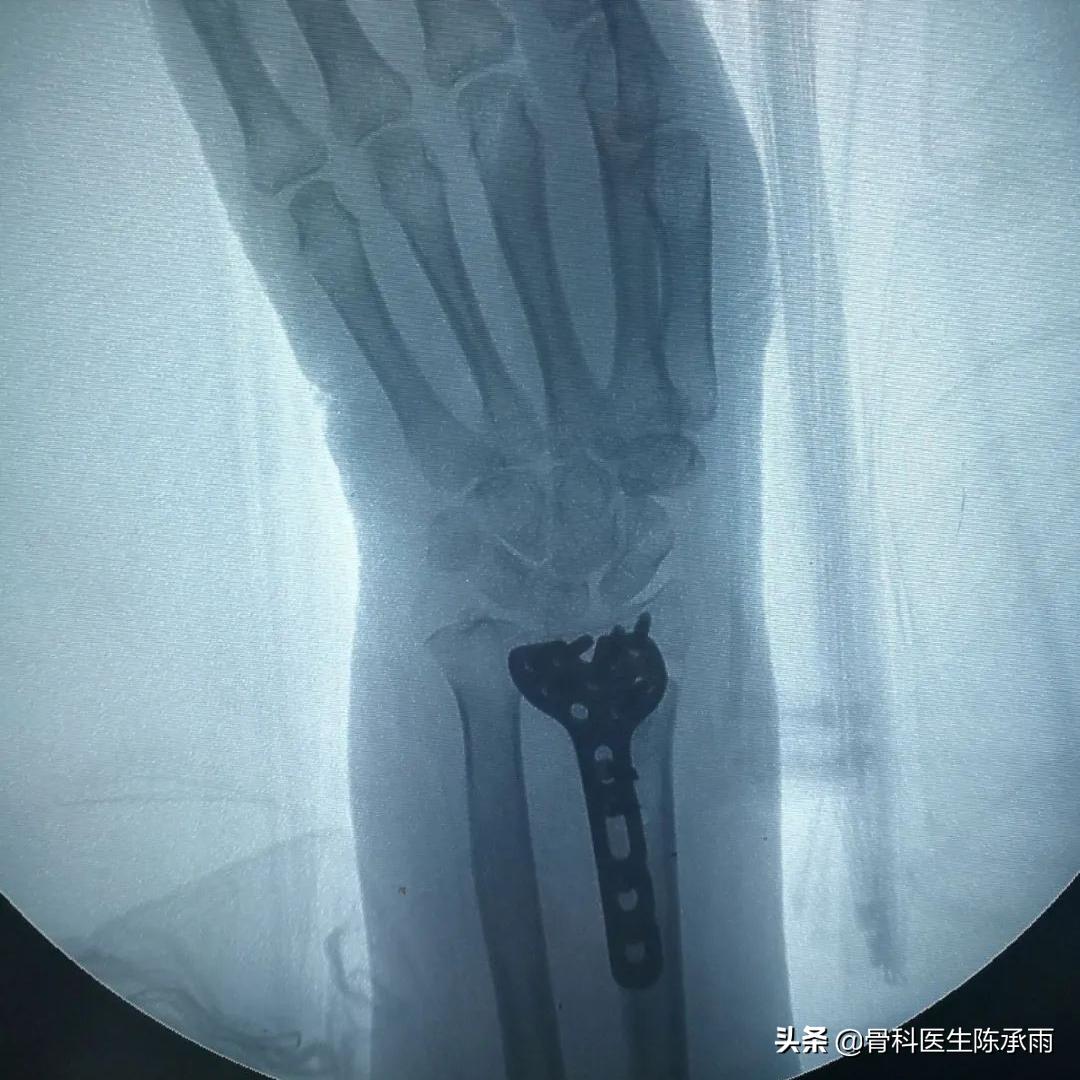

制定手术方案,术中见骨折愈合稳定,骨质疏松严重,远尺桡关节脱位固定,腕关节旋转受限。

原有骨折关系已不能找到,软组织粘连严重,骨折较疏松,尽量达到功能复位。

术后患者恢复良好,患者满意,终于露出久违的笑容。